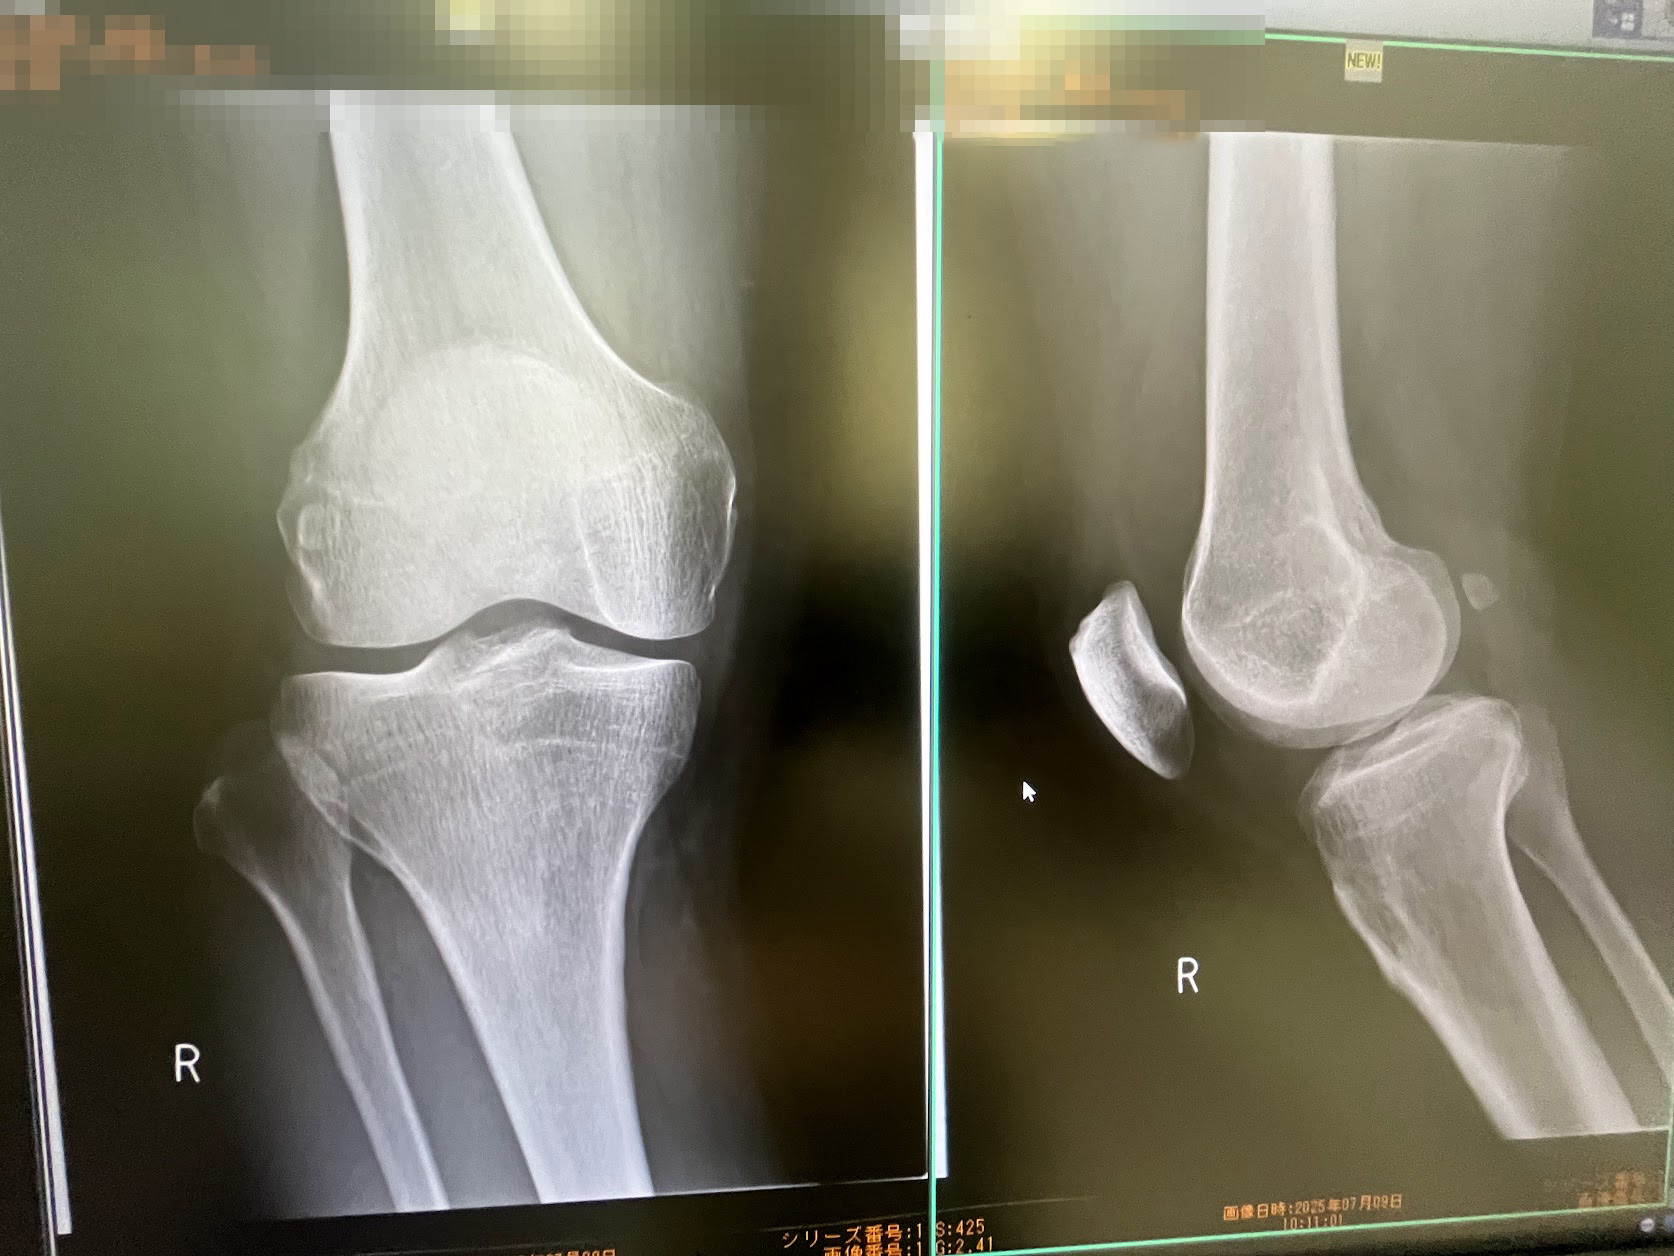

右膝半月板損傷の故障を抱かえたままのスタートとなり(この写真ではヒビが写っていません、MRIで判明しました)手術も覚悟しましたが幸いな事にヒビが直線だったため手術でなく自然治癒を待てとの事でした